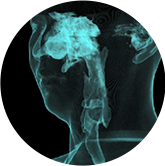

VR体绘制重建

气道三维影像重建